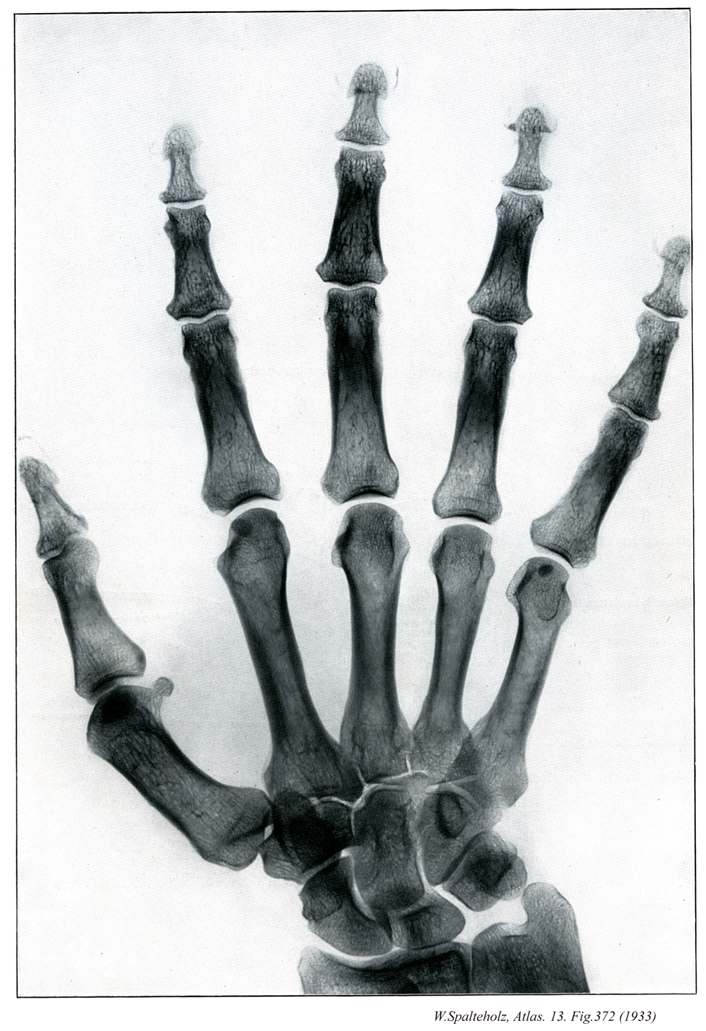

372

- 372_00【Hand手;テ Manus】

→(手は上肢のうち橈骨手根関節より遠位の部分。手根と中手に区別され、手根と中手の前面を手掌、後面を手背という。皮膚節において第六頚神経、第七頚神経、第八頚神経のレベル。)